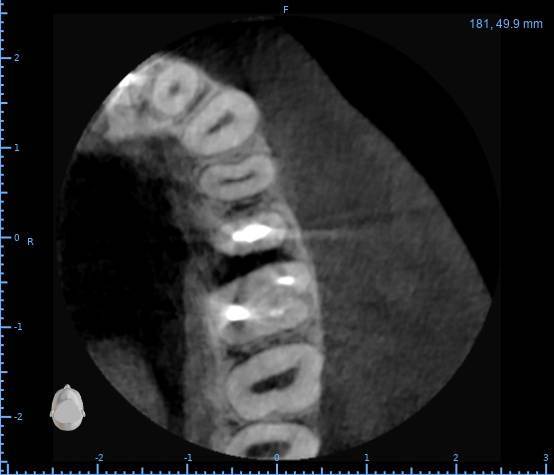

Здравствуйте, появился полгода назад свищ на десне, заполняется и лопается, затягивается и снова появляется, спустя пару месяцев обратился в стоматологию, на снимке ничего критичного не увидели, отправили домой наблюдать тип, еще прошло 3 месяца, так и не проходит и хуже не стало, болей нет никаких, только небольшая если трогать в районе свища, пойдя в другую стоматологию, сделали снимок и так же непонятно что и почему, пошел на КТ, и обратно в стоматологию, есть какая то полость, можно попробовать но нет гарантии, что пройдет, прикрепляю снимок К

ТРезультаты и плюс программа для открытия